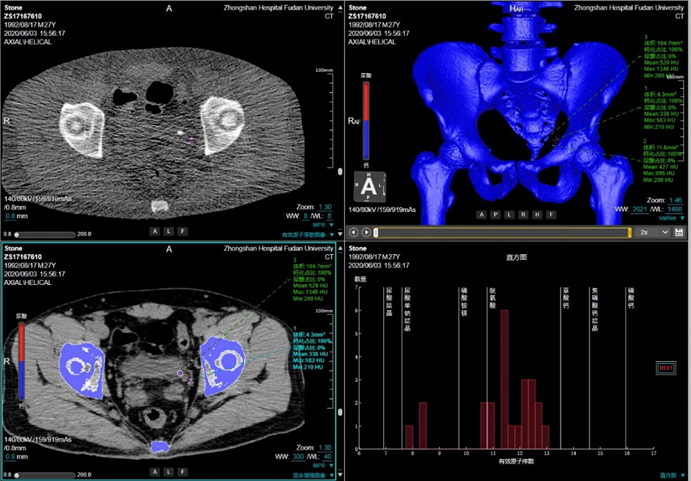

功能成像方案

能谱成像技术:分析人体病灶的组织成分、组织特性,为影像诊断提供常规CT无法提供的重要信息,如进行痛风石检测、泌尿系结石成分分析、碘与钙质区分、肿瘤同源性鉴别等。

泌尿系结石成分分析

联影ct怎么样【小南快讯】辐射低、成像快、更精确!CT届的“天花板”——320排640层超高端CT落户奉中心!_https://www.jmylbn.com_新闻资讯_第19张